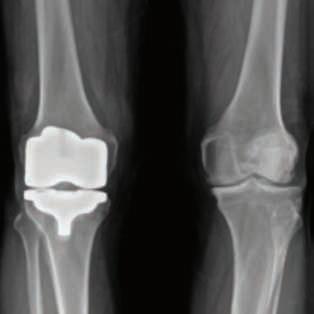

Nancy Antone, 72, is one of our grateful Campbell Clinic trauma patients. She was working in her yard when she fell in late 2022, breaking the top of her right femur. During the next year, she underwent five surgeries—once to implant a metal rod, once to address an E.coli infection, a third operation to replace the incorrectly situated rod with an antibiotic one, a fourth operation to implant an all-new metal rod, then finally a knee replacement. After her original operation at Baptist-Desoto, Ms. Antone consulted with Dr. Marc Mihalko, then was under the care of Drs. Cosgrove and Gregory Dabov.

During the 2023 American Association of Hip and Knee Surgeons (AAHKS) Annual Meeting, Campbell Clinic’s Marcus C. Ford, MD and William Mihalko, MD, PhD, were awarded the AAHKS Clinical Research Award for investigating the safety and clinical efficacy of extended postoperative tranexamic acid (TXA) use in total knee arthroplasty (TKA). Other contributors in this study were Mateo Kirwan, MD; Zachary R. Diltz, MD; Derek T. Dixon, BS; Carlos A. Rivera-Peraza, BS; Christal J. Gammage, PhD; James Harkess, MD; James Guyton, MD; and John Crockarell, MD.